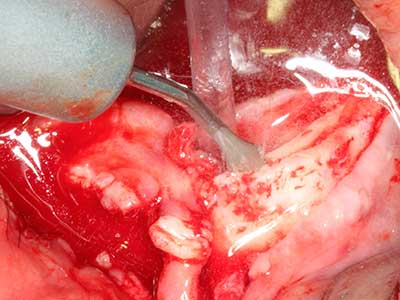

Quando le procedure chirurgiche vengono eseguite sull'osso nelle immediate vicinanze di strutture sensibili, come vasi sanguigni o nervi, gli strumenti rotanti pongono un rischio significativo di lesione iatrogena. I dispositivi piezoelettrici possono essere utili per la preparazione delle coperture ossee e la rimozione del tessuto duro in prossimità dei nervi, in particolare per la loro esposizione dopo una lesione iatrogena, ma anche durante la lateralizzazione dei nervi per le procedure di resezione e ricostruzione o il posizionamento di impianti (figg. 17-20). Il contatto leggero tra puntina piezoelettrica e nervo non causa generalmente danni, ma se si procede senza prestare attenzione con movimenti a sega o raccordi con residui di substrati ossei possono verificarsi danni al nervo temporanei o anche permanenti. Il rischio di danno, tuttavia, è considerato sostanzialmente inferiore al rischio presente utilizzando seghe o frese (Pereira, Gealh et al. 2014).